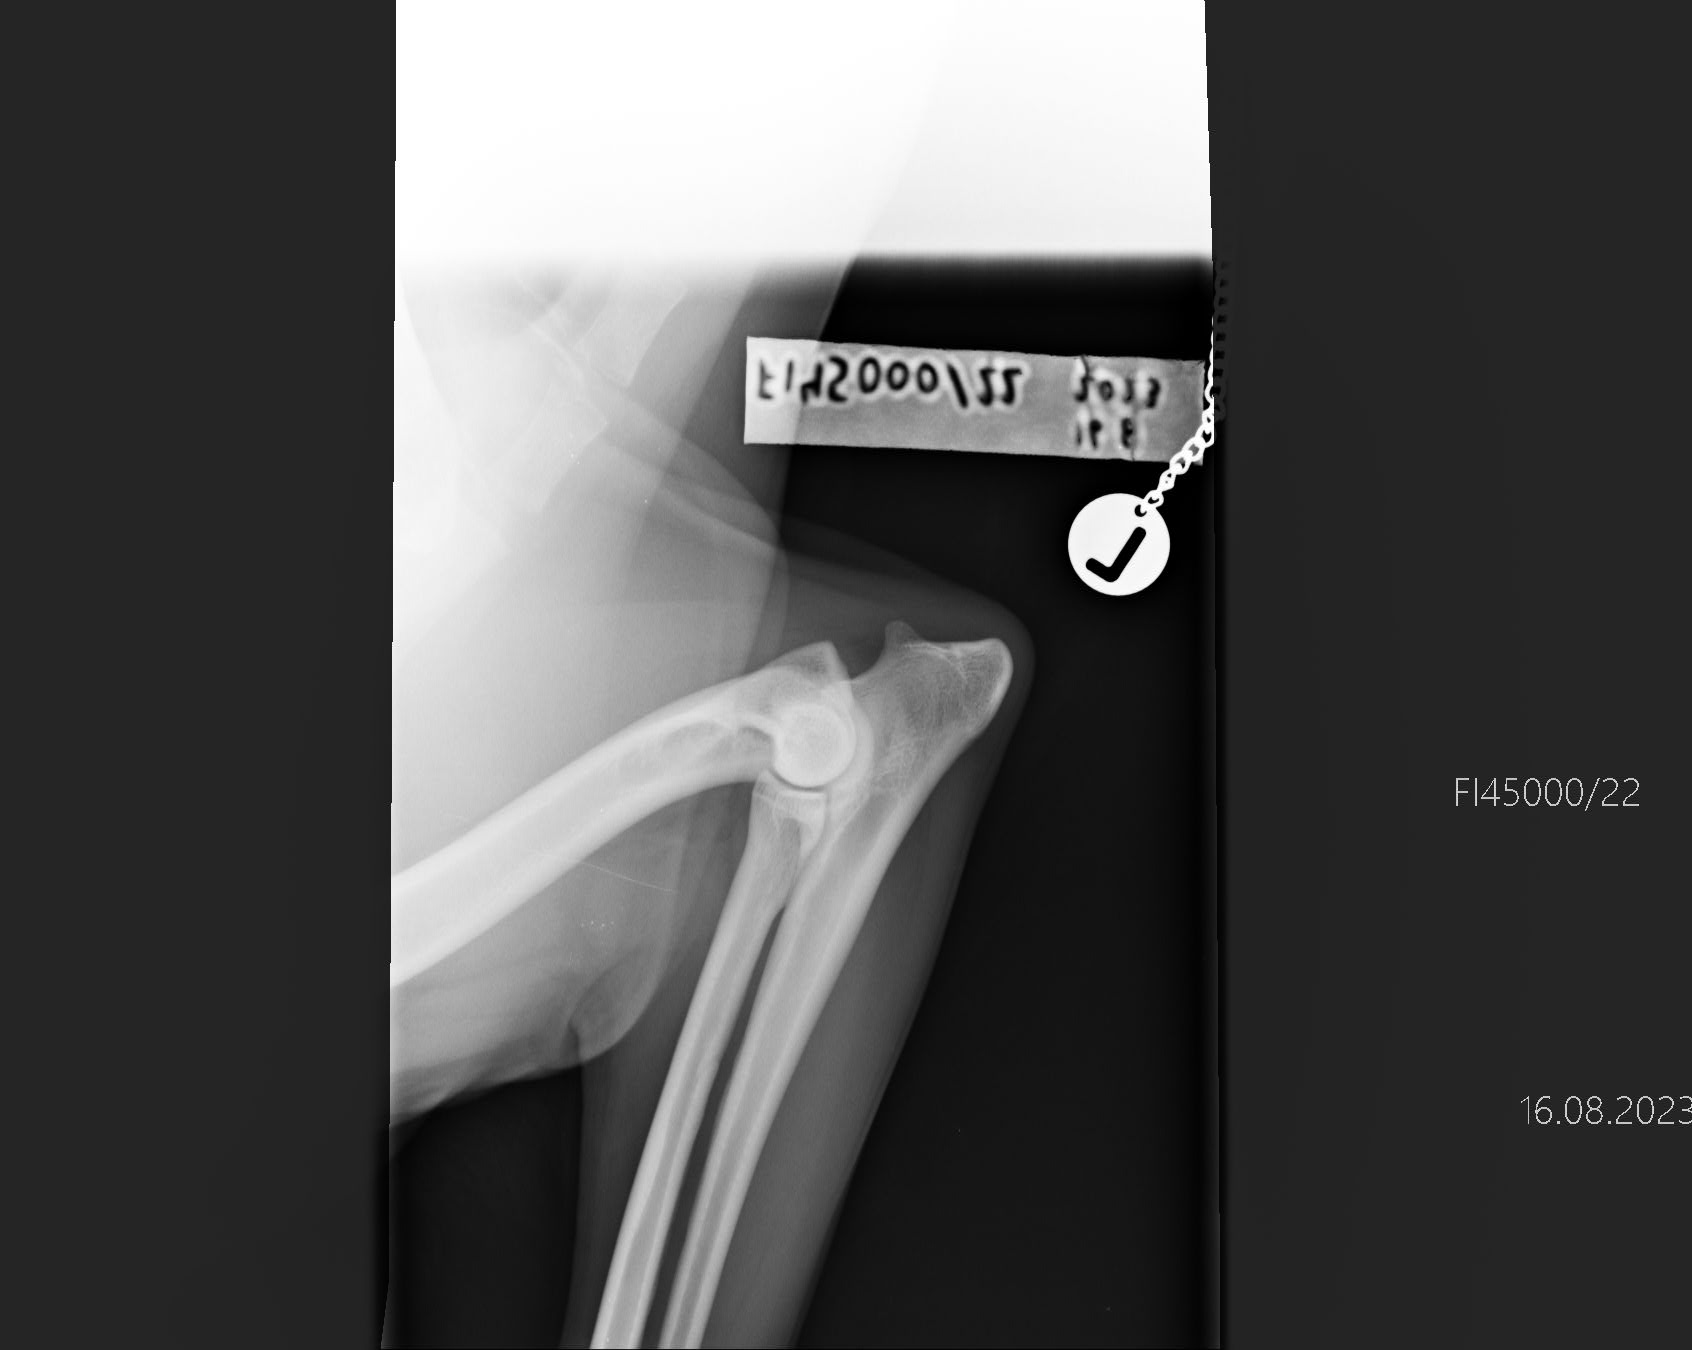

Kyynärät

— 0/0

«

Selkä

— LTV0 VA0 SP0«